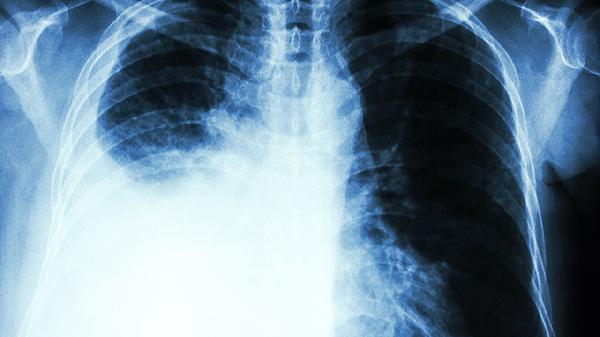

1、普通胸片查不出早期肺癌

王先生每年单位体检胸片都"正常",其实1cm以下结节检出率不足15%。低剂量螺旋CT才是金标准。

2、肿瘤标志物正常≠安全

他的CEA指标始终在参考值内,但小细胞肺癌患者该指标阳性率仅30%左右。